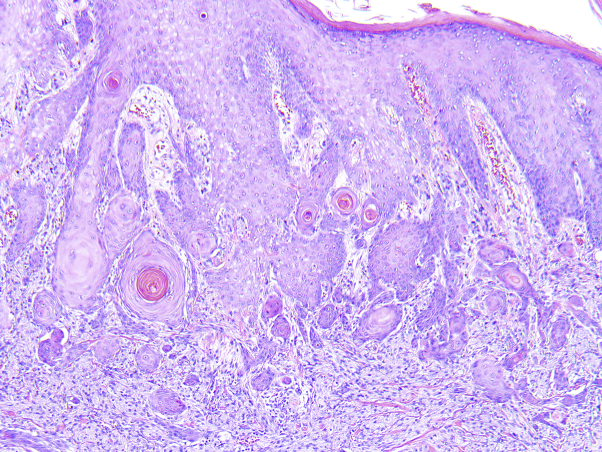

Fig 2.

Histopathology of granular cell tumor. Nests of cells with abundant eosinophilic granular cytoplasm separated by bands of collagenous stroma. Pseudoepitheliomatous hyperplasia can be observed in the overlying epidermis. (Hematoxylin-eosin stain; original magnification: ×40.)